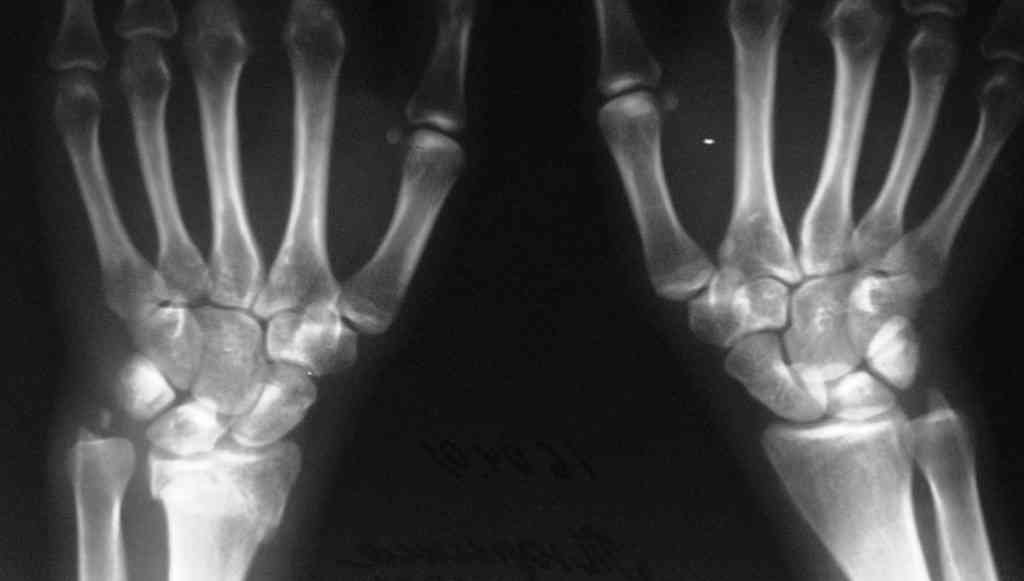

У больного/ой кроме перелома лучевой кости и шиловидного отростка локтевой, разрыв дистального радиоульнарного сочленения, перелом ладьевидной кости и ладьевидно-полулунная диссоциация.

Если позволите свое мнение, не стал бы лечить аппаратом эту травму, перелом луча не консолидировался: открытая репозиция+ костная пластика+ пластина, синтез ладьевидной кости, по возможности шов ладьевидно полулунной связки,

если восстановить связку не представляется возможным, фиксация 2 спицами.